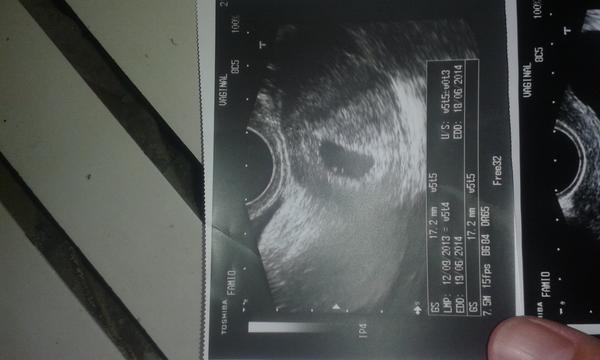

@evaburesova20 tak takhle to u me vypadalo v 6tt

@evaburesova20 a takhle o dva (nebo tri? ) tydny pozdeji. Bylo i krasne srdicko.

@evaburesova20 omlouvam se, fotim jen mobilem 🙂

@ivatko0406 dekuji moc za fotečku,přesne takto to vypadalo ted na ultrazvuku 5t.+3 jsem už o moc klidnejsi.pekny den a diky

@evaburesova20 tak to jsem rada, ze te to uklidnilo 🙂. Dr. mi tehdy rikal, ze je vse normalni, tehotenstvi je tam kde ma byt - tedy v deloze. Nicim vic me nedesil, proste - prijdte za dva tydny a uvidime uz snad i srdicko. Jisteze je vzdycky moznost, ze bude neco spatne. Ale dr. se zda se drzel toho, ze klidna maminka je dulezity bod celeho tehu. Nemazal mi med kolem pusy, ale ani nedesil. Tak bud klidna a na pristi kontrole uvidis, jak velka bude zmena!